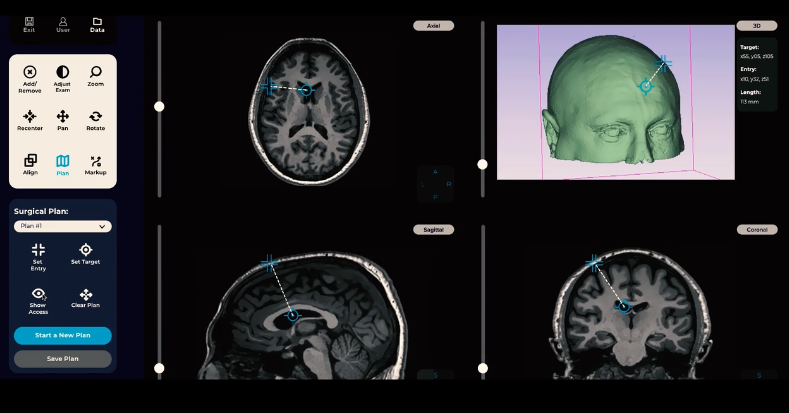

作为领先的手术机器人开发商,AiM 公司曾在2022年8月推出了业界首个MRI兼容神外手术机器人样机,该系统以精度为重点,便携,可与任何MRI诊断设备一起使用。

据了解,AiM 开发的业界首个MRI兼容神外手术机器人,旨在改善接受神经外科治疗功能性脑部疾病(帕金森氏症、癫痫等)和癌症的患者的预后,同时通过消除错误和将手术时间缩短多达 50% 来为医院节省成本。

借助术中MRI设备成像,该系统能够完成机器人的精准操作,包括对准、插入和操作神经外科器械,其便携式的系统能够很容易地安装在任何诊断或介入MRI中,或者在传统的基于手术室的神经外科环境中用作机器人平台。

同时,还可以进行神经外科实时动态手术,在术中随时随地评估神经功能,校正神经缺损等。并能精准对病灶(包括肿瘤等)切除,减少对周围健康组织的影响,此外兼容移动MRI平台,可以解决患者转运时遇到的问题。具有成本效益,简化和差异化。